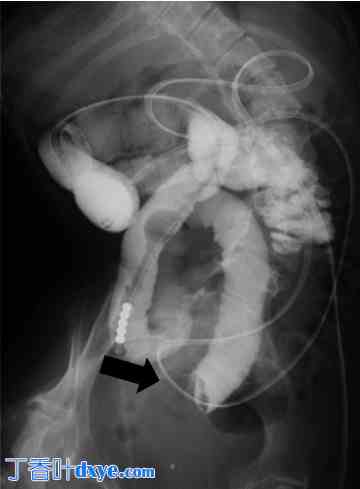

患者经胃瘘插入肠梗阻管以减压肠道,但症状未得到缓解。入院后第11天,经肠梗阻管进行的增强X光检查显示肠道内造影剂滞留,肠腔内可见圆形阴影(图2)。入院后第19天,患者决定进行手术治疗,初次腹腔镜检查全小肠和大肠,发现空肠内有一肿块嵌顿(图3(a))。对肿块进行肠切开术,取出两枚胆结石,尺寸分别约为2.5 × 3.5 cm和3.0 × 2.5 cm(图3(b))。术前未进行腹部超声检查。

图 2.

使用肠麻痹管进行造影放射学检查。造影放射学检查显示肠道内造影剂滞留,肠腔内可见圆形阴影(箭头所示),直径约 2.5 cm。